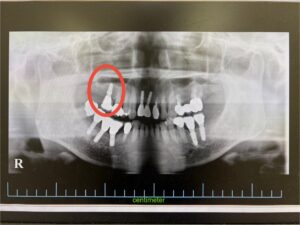

<インプラント実例掲載>サージカルガイドを用いてインプラントを埋入した症例

今回は、60代女性の方の症例をご紹介いたします。

患者様は以前、他院で右下に3本、前歯に2本のインプラント治療を受けられており、当院では左下に2本のインプラントを埋入し、そちらは良好に機能していました。

今回は「右上の奥歯が無く、うまく噛めない」というお悩みでご来院され、インプラント治療を希望されました。

CTによる診査・診断の結果、右上顎の骨量が不足していたため、骨造成を併用しながら“ソケットリフト法”を選択しました。

慎重に処置を進め、同日に安全にインプラント埋入まで行うことができました。

術前